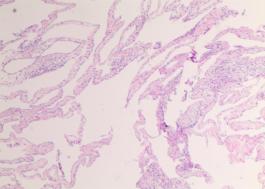

CT提示:子宫左后方水样密度灶,周边见腹膜包裹,考虑良性病变(图2)。遂行腹腔镜下探查术,术中见盆腔内少量游离淡黄色积液,子宫左后方道格拉斯窝见囊性病灶大小约8cm×6cm×6cm,内有纤维分隔带,见清亮液体,子宫前后壁表面见多发散在滤泡样渗出,直径在0.5cm-2cm不等,壁薄透明,内见淡黄色液体,遂手术切除子宫后方及子宫前后壁可见病灶。探查大网膜、阑尾区等未见明显病灶。

妇科蛋白膜怎么用这种妇科肿瘤无特异性,复发率高,有这些症状的姐妹小心_https://www.jmylbn.com_新闻资讯_第2张图2 CT见子宫左后方水样密度病灶,

周围见腹膜包裹(箭头所示)